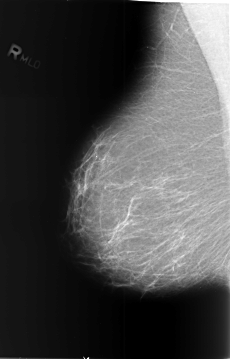

B_3372_1.RIGHT_MLO

RIGHT_MLO LINES 5736 PIXELS_PER_LINE 3680 BITS_PER_PIXEL 12 RESOLUTION 50 NON_OVERLAY